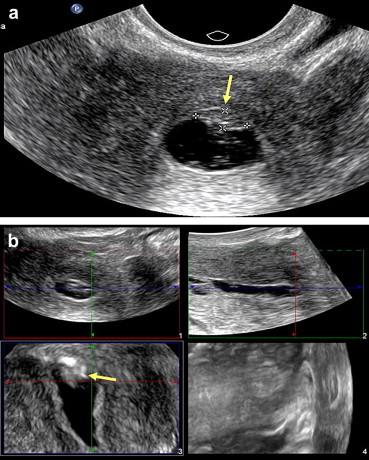

Fig. 4.

Assessment of the uterine fundus. (a) 2-D sonohysterography: Axial scan of the uterus reveals evidence suggestive of a small lesion in the fundus (arrow). (b) 2-D sonohysterography: the fundus lesion is clearly visualized (arrow). The irregular appearance of the wall is caused by peristalsis.

Fig. 5.

Value of coronal-plane scans. (a) A polyp located in the tubal angle can be fully explored on the coronal scan (arrow). (b) A submucosal myoma (associated with menometrorrhagia) can be seen protruding into the cavity of uterus. The fundus malformation can be seen better on the coronal reconstruction (arrow).